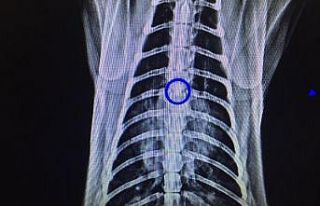

Adli kurumlara yaptığı şikayet üzerine savcılıktan koruma altına alındığına dair bir belge geldiğini anlatan İclal Ş., “O belge geldiğinde de ciğerlerimden hastanede yatıyordum. O belgeyle eve geldiğimde annem kapının kilidini değiştirmiş. İçeriye giremedim. Beni evden attı. Üç aydır sokaktayım. Benim kronik rahatsızlıklarım var, kolojen doku ve hareket sistemi, buna eklenen akciğer, böbrek oldu. Hastanede bir keresinde 15 gün, 1,5 ay önce de 10 gün yattım. Bu arada da eve gidemediğim için bir süre üniversitenin acilinin kantininde kaldım. Şimdi de sokaktayım. Kronik rahatsızlığım 50 yıldır devam ediyor. Solunum makinelerim evde. Bu yaştan sonra kendime bir yer bulup da oturma imkanım yok” ifadelerini kullandı.